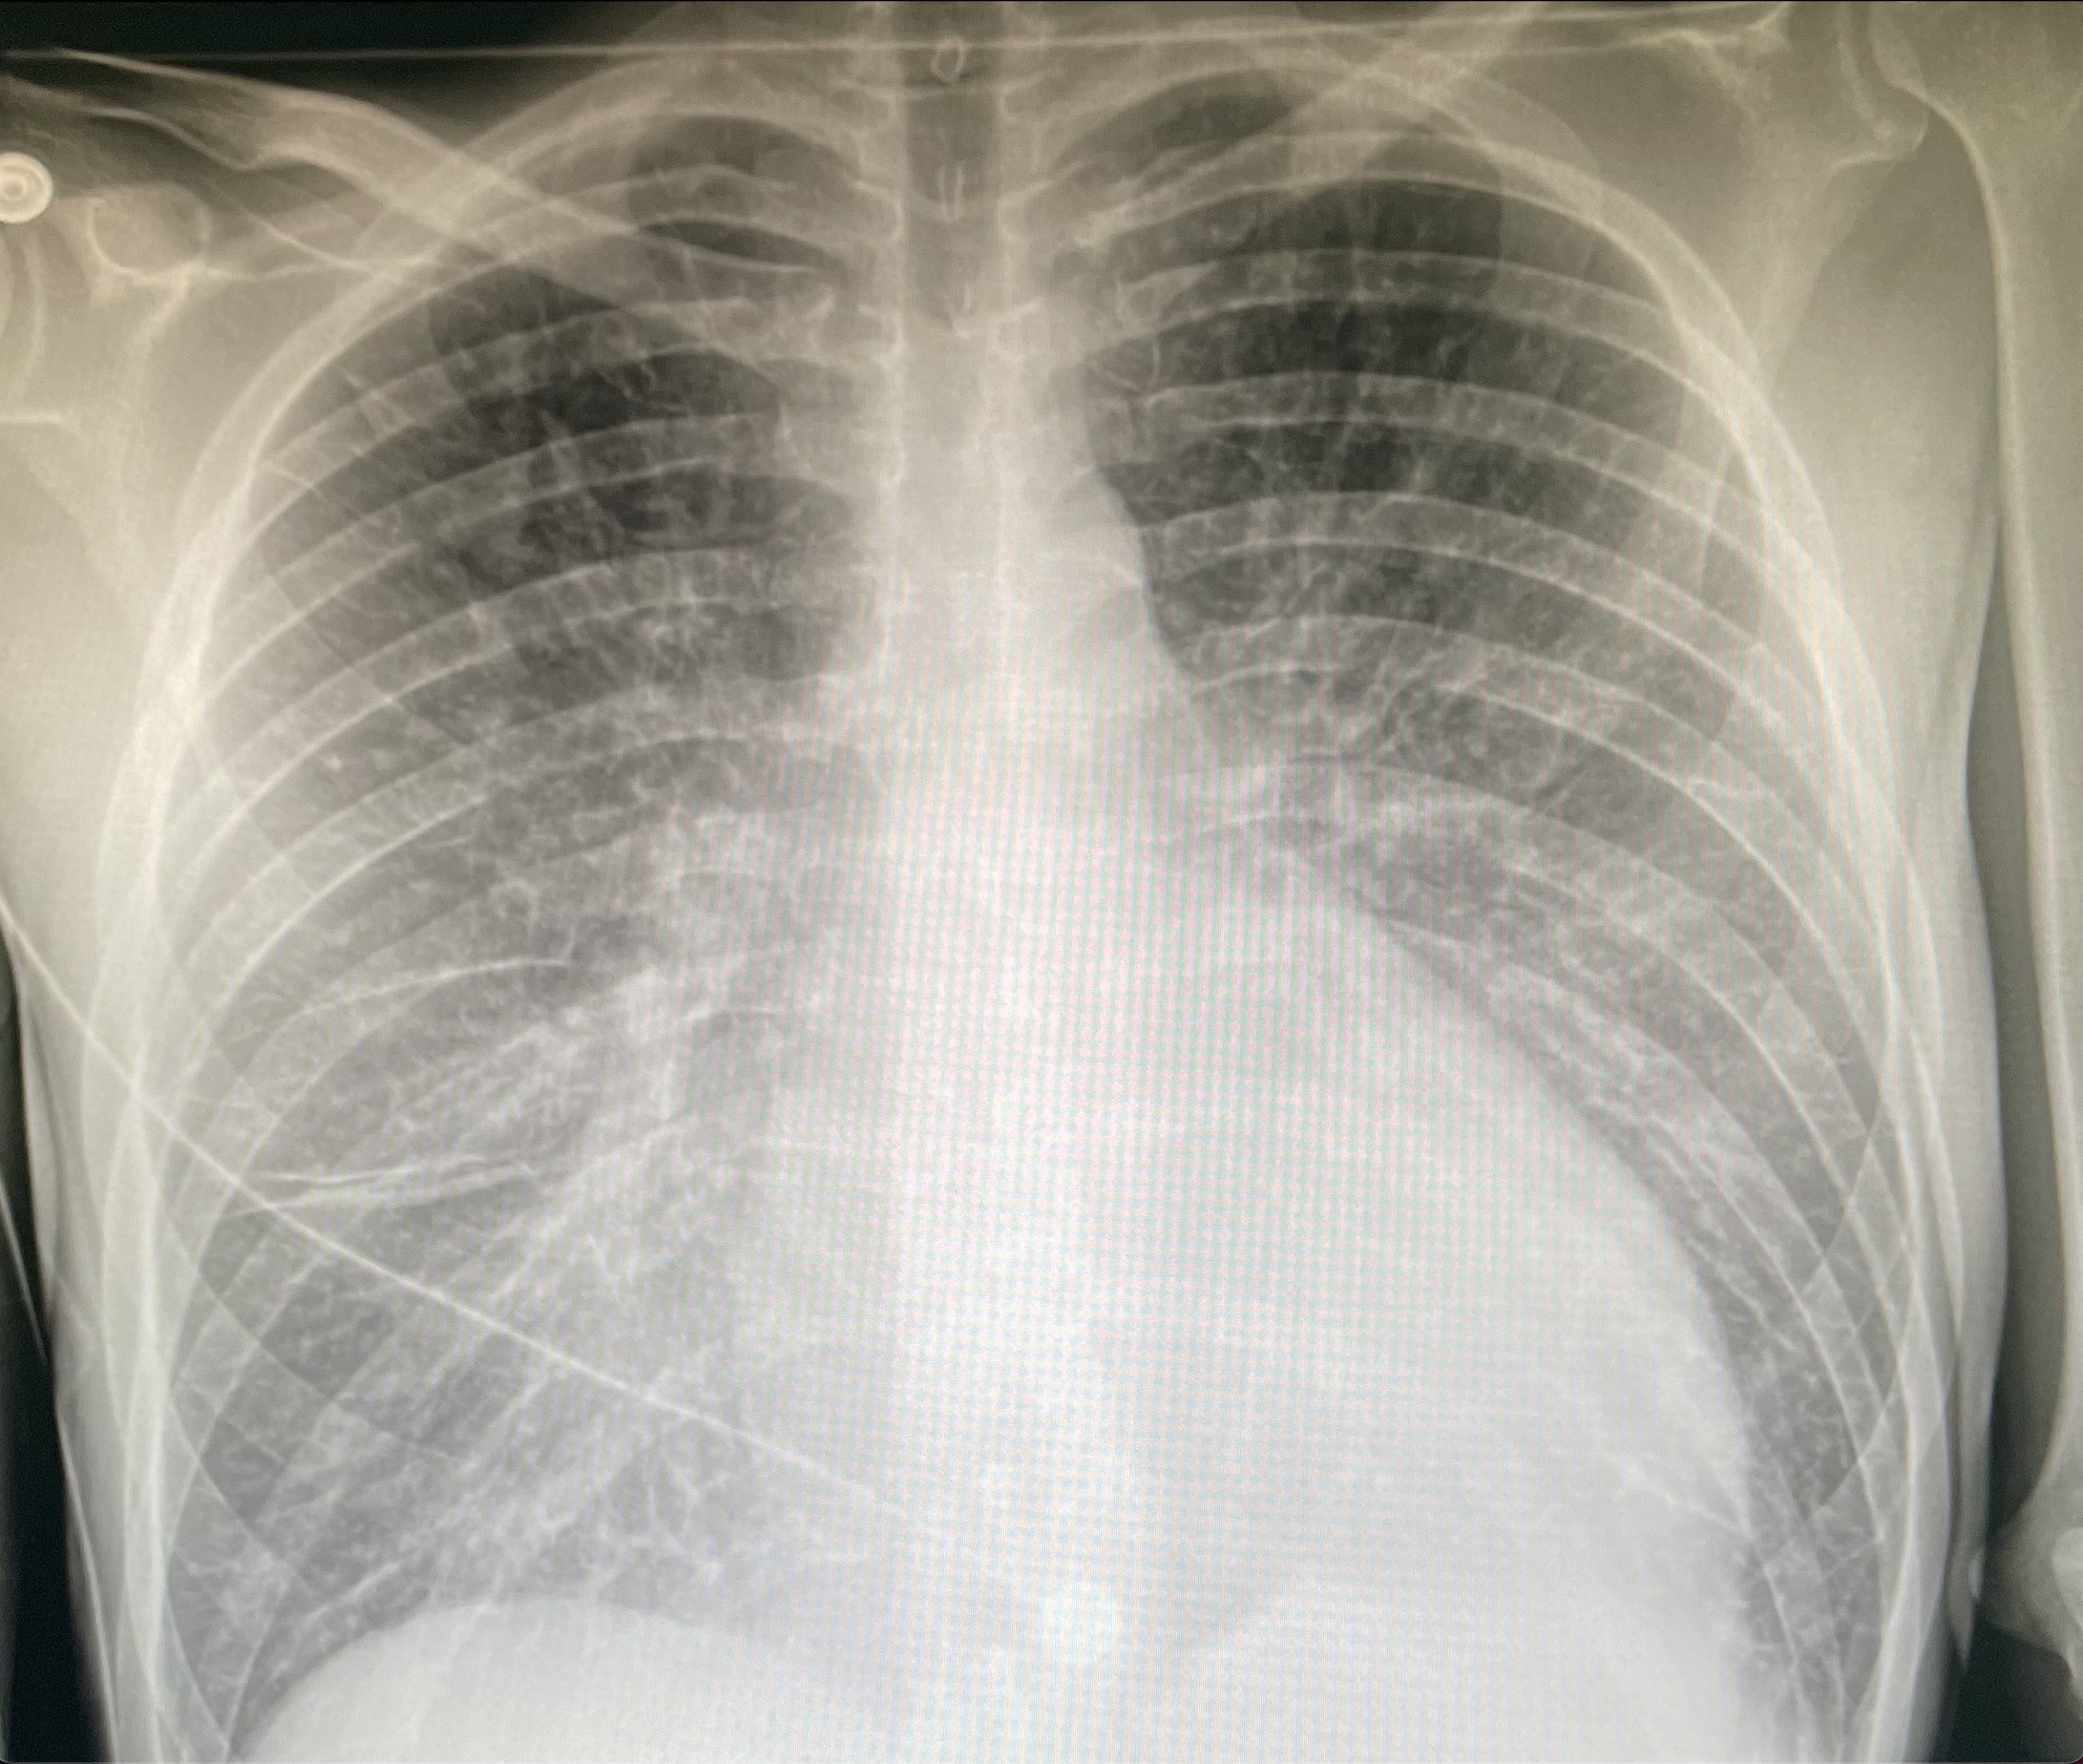

RX cardiomegalia y patrón de redistribución vascular.